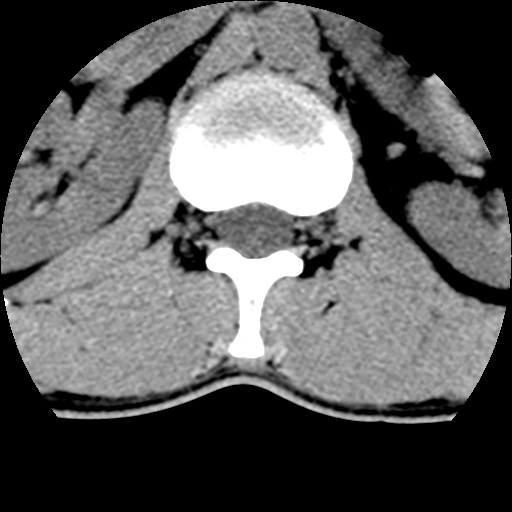

男,31岁,从6米高处坠落伤两天,腰背部疼痛,临床要求ct扫描胸10-腰1。请大家帮忙看看骨质有问题吗?

t12、l1锥体前缘轻度楔形变,平扫示椎体前缘骨小梁欠规整,第9幅图示椎体前缘骨质不连续,结合外伤史考虑椎体轻度压缩骨折。

从上查骨窗第九片椎体前缘皮质显示断裂.压缩骨折?